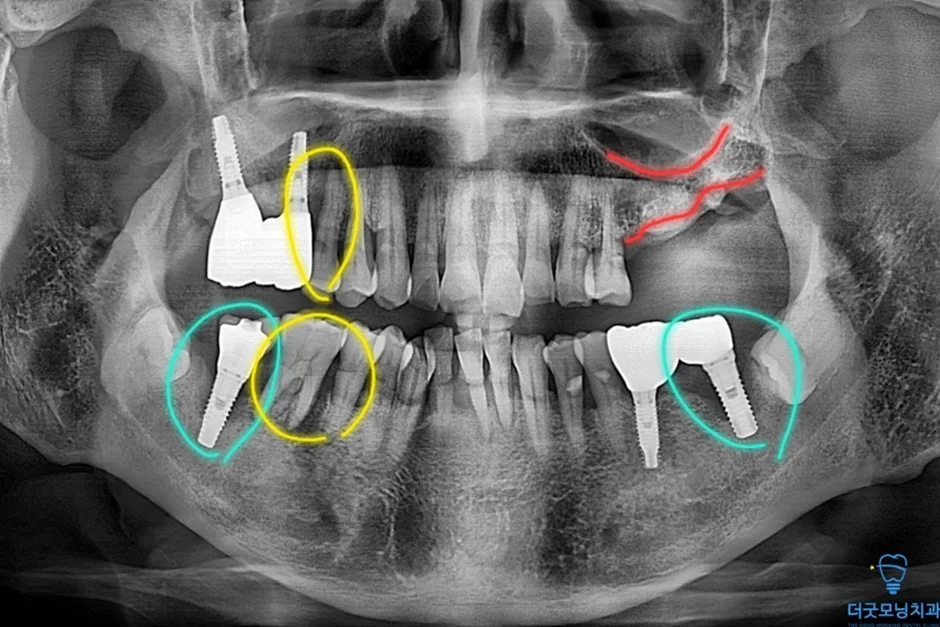

2. 검진 결과 — 파노라마 엑스레이 & CT 분석

먼저 파노라마 엑스레이와 CT를 통해 구강 전체 상태를 확인하였습니다.

■ 왼쪽 위 (상악 좌측)

상악동이 많이 함기화되어 있어 상악동 골이식(치조정 접근 상악동 거상술)이 반드시 필요한 상태였습니다. CT 확인 결과 가용골이 매우 부족한 것이 명확히 확인되었습니다.

■ 오른쪽 위 (상악 우측)

치주염으로 인해 치아가 흔들리는 상태였으며, 발치 후 즉시 임플란트 식립을 계획하였습니다.

■ 아래 양쪽 (하악 좌·우측)

임플란트 주위염이 발생하여 기존 임플란트를 제거하고 재수술이 필요한 상태였습니다. CT 상 신경관까지 어느 정도 거리가 확보되어 재수술은 무리 없이 진행 가능하였습니다.

노란색 표시처럼 임플란트 식립 잘 마쳤습니다.

두 번째 수술에서도 임플란트가 CT 상에서 확인될 만큼 정확하고 안정적으로 식립되었습니다.